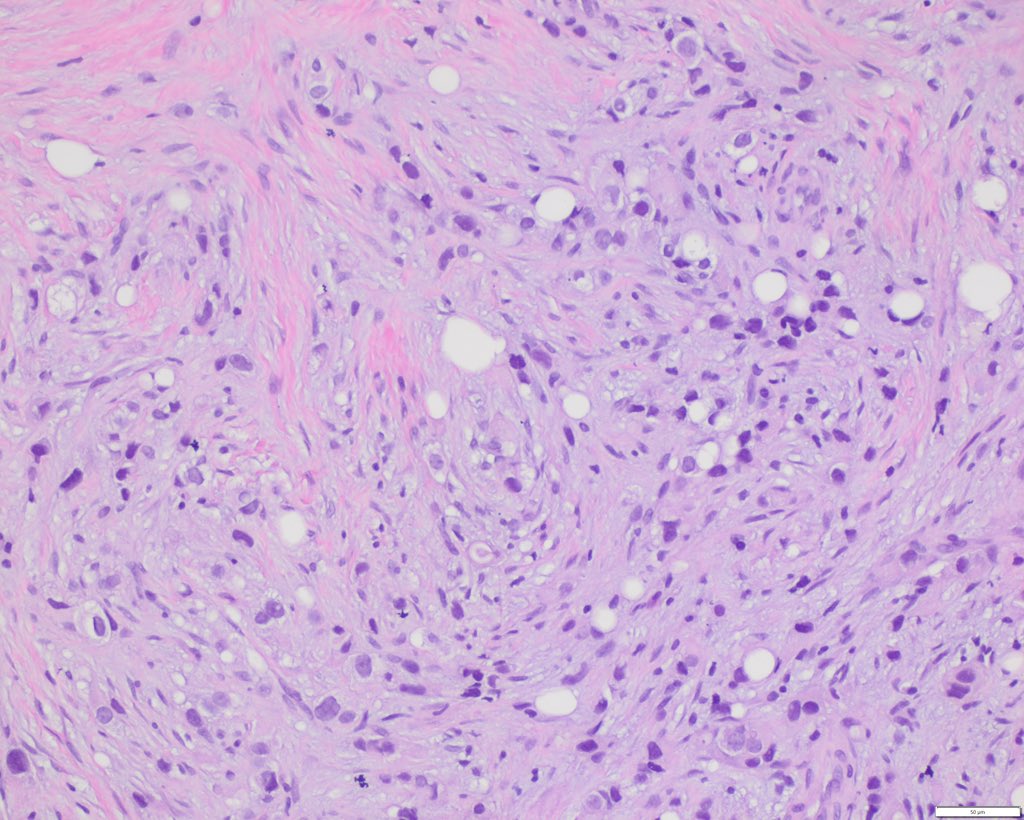

58 F skin lesion on left occipital scalp. No tumor anywhere else in the body #dermpath #dermtwitter #BSTpath #PathTwitter @HENRYY_MD @vhnguyenmd @Coluchkaaaaa @DrGeeONE @JamesSampson123 @Meghna0630 @PoojaSMD @MELanocyteMD @forthejon